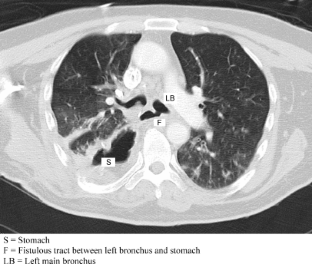

Fig. 1